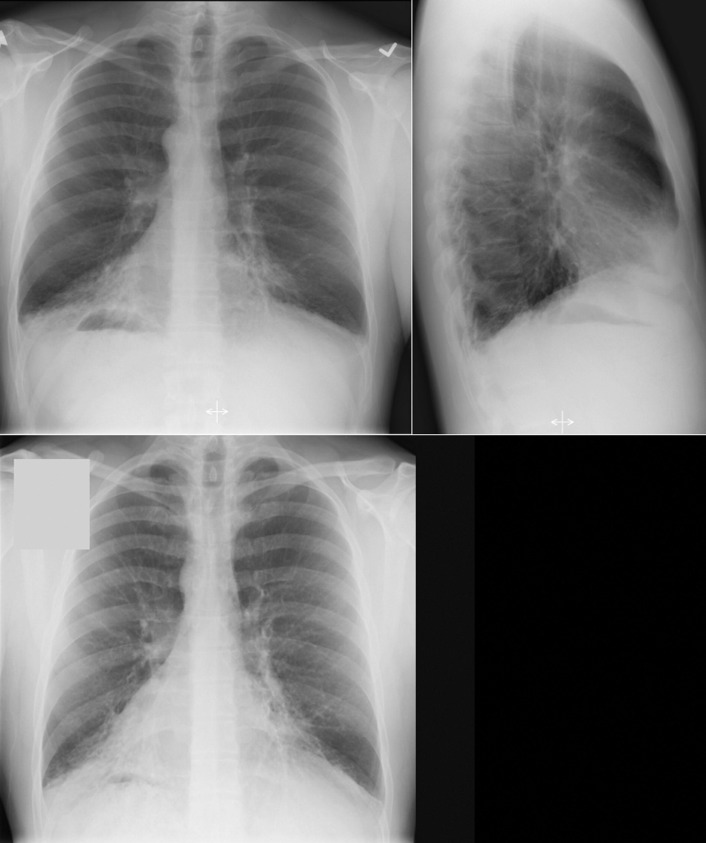

Situs refers to the position/arrangement of the thoracic and abdominal organs ( Figs 20-1 to 20-5 ). The posteroanterior/frontal chest radiograph is able to depict the location of the heart, the left ventricular apex, the aorta, and the gastric air bubble, and it may thereby determine situs.

Situs solitus (normal): left apex and left-sided stomach ( Fig. 20-6 )

Figure 20-6

In this chest radiograph from an infant, the heart is displaced to the right side, not the apex. The position of the gastric air bubble is ambiguous. The responsible lesion is a large left-sided diaphragmatic hernia, with the stomach and bowel moved into the left chest, displacing the otherwise normal heart and rendering the gastric air bubble obscure.